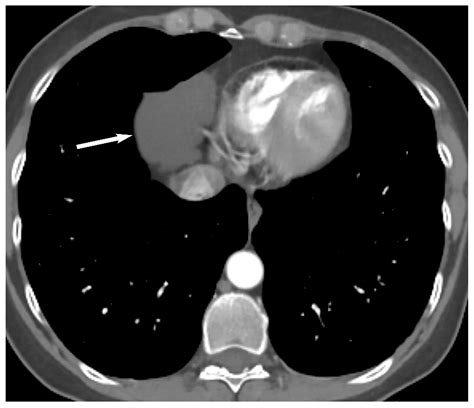

The discovery of a Mass Anterior Mediastinum—a growth located in the front compartment of the chest cavity—can be a daunting experience for any patient. The anterior mediastinum is a critical anatomical space bordered by the sternum in the front, the heart and great vessels in the back, and the lungs on the sides. Because this area houses essential structures such as the thymus gland, lymph nodes, and parts of the thyroid, any abnormal growth requires prompt clinical evaluation to determine its nature, whether benign or malignant.

To grasp the significance of a Mass Anterior Mediastinum, one must first understand its anatomical context. The mediastinum is divided into three sections: anterior, middle, and posterior. The anterior division, also known as the prevascular space, is the most common site for various tumors and cysts. Because this space is relatively small, even a slowly growing mass can quickly compress adjacent organs, leading to noticeable symptoms.

When a patient presents with symptoms such as persistent cough, chest pain, or difficulty breathing, medical professionals will initiate a diagnostic journey to confirm the presence of a Mass Anterior Mediastinum. Initial physical examinations are often followed by advanced imaging techniques, which are crucial for mapping the size, shape, and relationship of the mass to vital structures.

CT Scan (Contrast-enhanced) The gold standard for determining the exact location and extent of the mass.